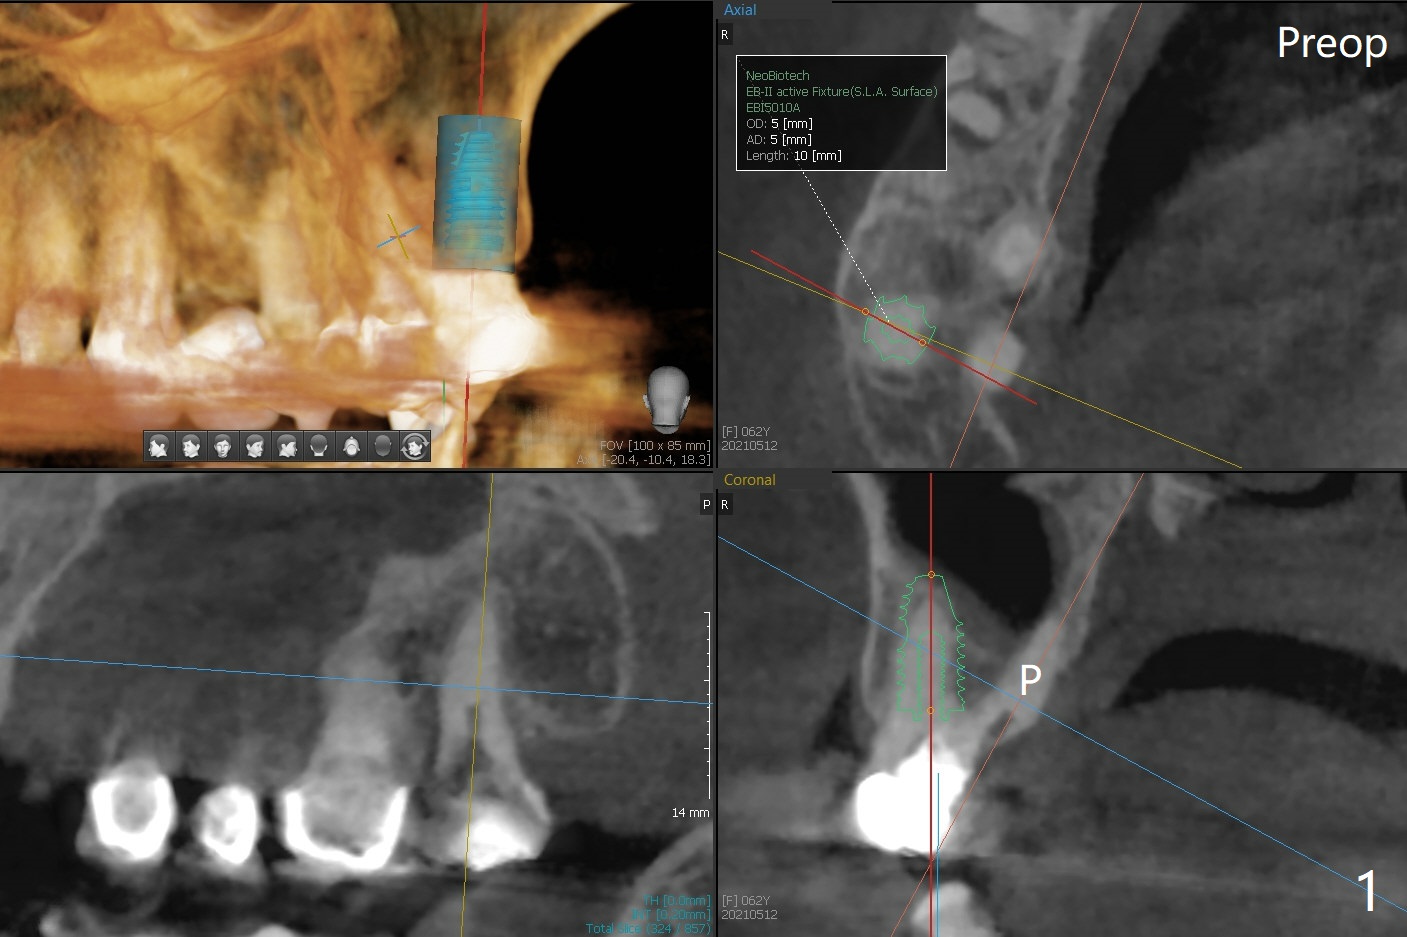

When the tooth #2 is extracted, there is sinus perforation in the palatal apex, consistent with preop CT (Fig.1: P). There is no bone shaving associated with drill sequence in the buccal socket (until 3.5x8.5 mm). With sticky bone and 4.5x10 mm IS dummy implant, sinus lift does not happen. Sinus floor perforation is felt when a 2.2x10 mm drill is used slowly. But air leaks from the palatal socket. With bone graft, a 4x10 mm dummy implant lifts the sinus (Fig.2). After further graft and 4.5x10 mm dummy implant, a 5x11 mm final implant is placed with 15 Ncm with sinus lift (Fig.3,4 *). Following abutment insertion, sticky bone is packed around the implant and abutment (Fig.5,6 S). Prior to final implant placement, a small piece of PRF and collagen and Osteogen Plugs are placed in the palatal socket for repair. Before discharge, there is mild nasal hemorrhage.